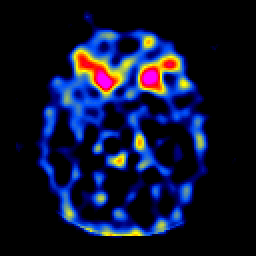

SPECT TL Study #6 -- Slice #23